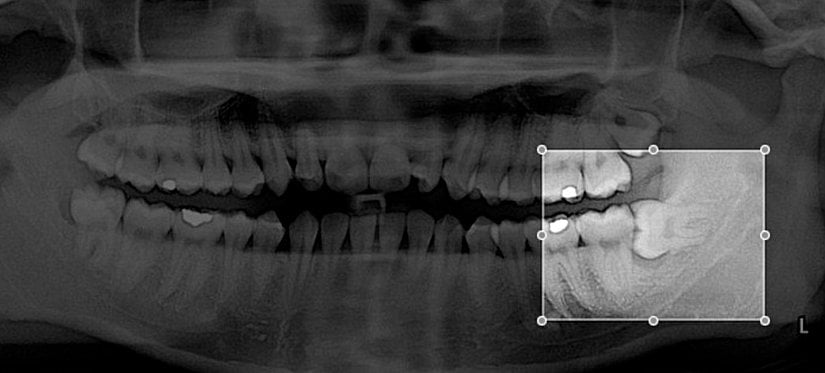

Prosedürün uygulanmasına alıcı sahadaki dişin çekilmesiyle başlanır. Donör sahadan da dişin çekilmesi ve alıcı sahanın donör dişe göre uyumlanması ve dişin alıcı bölgeye sabitlenmesiyle ilk aşama tamamlanmış olur. Prosedür kontrol seansları ve gerekli görülmesi durumunda dişe kanal tedavisi uygulanmasıyla son bulur. Prosedürdeki en önemli aşama, transplante edilecek dişin çekilmesi ve yerleştirilmesi arasında geçen süre olarak düşünülmektedir. Dişin yerleştirileceği alanın dişe göre uyumlandırılması bazen çok uzun sürmekte ve tedavinin başarısını düşürmektedir. Bu noktada tomografi ve 3 boyutlu yazıcılar devreye girmektedir.

Jop P. Verweij ve arkadaşları 2017 yılında yayınladıkları vaka raporunda 3 boyutlu yazıcıların ve tomografinin kullanımını vaka üzerinde sunmuştur. Transplante edilecek olan 3. molar dişin tomografi sayesinde modellemesi yapılmış ve 3 boyutlu yazıcıdan çıktısı alınmıştır. Bu model 3. molar dişin çekilmesinden önce alıcı sahanın donör dişe göre uyumlanmasını sağlanmış ve çekilen 3. molar diş hiç vakit kaybedilmeden alıcı sahaya sabitlenmiştir. Böylece donör diş olabilecek en kısa sürede transplante edilmiştir.